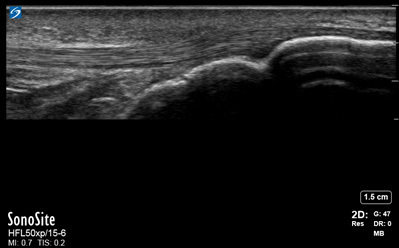

計測ー多重反射アーチファクトの画像